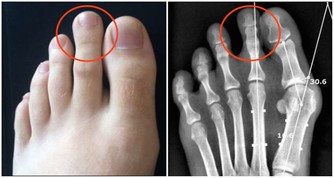

尾龍骨︰ 現在的人類,即使在沒有尾巴的情況下仍能好好平衡,因此不再需要尾巴。 男性乳突︰ 胎兒在首60天「還未定性」,因此是以同一模式發育,並長有乳突,但之後當它是一個男胎,代表男性的Y染色體產生作用後,胎兒的男性性器就繼續發育,胸部則停止發育。 智慧齒︰ 由於現代人類不用像原始人般咀嚼生的菜或肉,因此顎骨愈來愈小,因此不能容下智慧齒。 豎「雞皮」︰ 人類祖先有較多毛髮,因此當豎「雞皮」時,毛髮看起來更大,可以嚇退敵人。現在人類在受驚或寒冷時會豎「雞皮」,但作用已不如以前般大。 第三眼蓋︰ 近鼻子的眼角有一塊皮其實不用存在。雀鳥或爬蟲類仍保留該多出的半透明眼蓋,可一邊保護眼睛,一邊看東西。